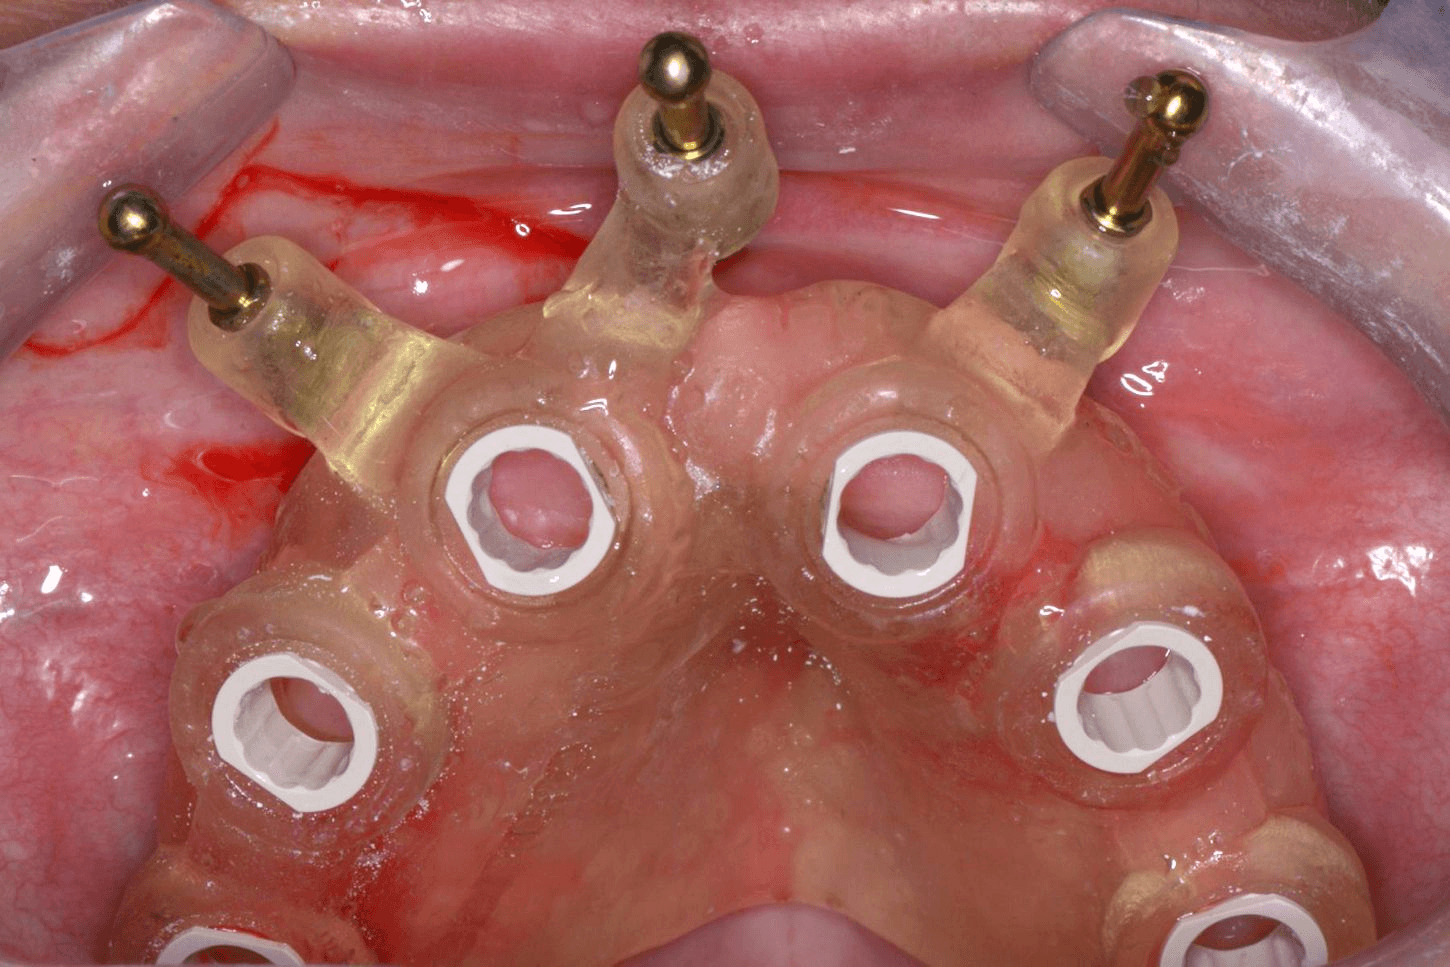

Designed for full-arch implant placement and usually fixed with anchor pins or screws after flap reflection.

After you confirm the final treatment plan, we create the appropriate surgical guide and proceed to 3D printing using high-end printers, or you can provide your own .STL file.